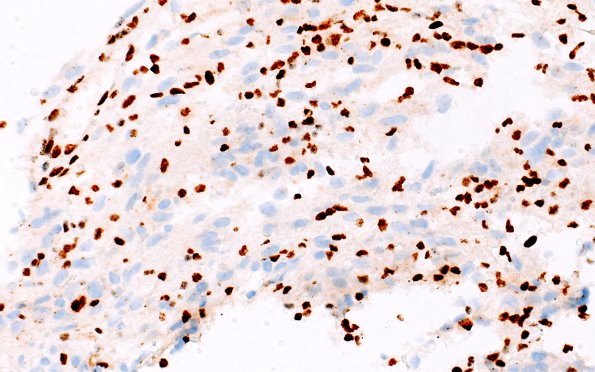

2D1,2 Tumor cells do not stain with ATRX; however, the background vasculature does. (ATRX IHC)